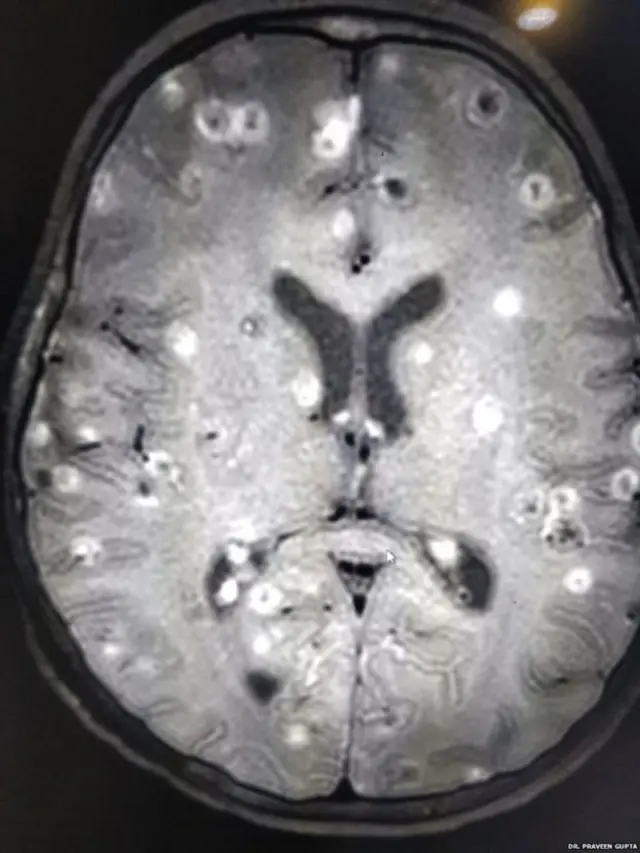

भारतमा एक आठ वर्षीया बालिकाको मस्तिष्कमा टेपवर्म अर्थात् नाम्लेकीराका एक सयभन्दा बढी फुल भेटिए।

"बालिकाको मस्तिष्कमा नाम्ले किराका सयवटा भन्दा बढी फुलहरू थिए। ती साना-साना समूहमा थिए।"

औषधि

डा. गुप्ताले भने, "बालिकालाई मकहाँ ल्याइँदा उनी अचेत थिइन्। सीटी स्क्यान गर्दा उनको मस्तिष्कमा सेता धब्बा देखिए। ती धब्बा अरू केही नभएर नाम्लेका फुल थिए। र, फुलहरू एउटा वा दुइटा नभई सयभन्दा बढी थिए।"

उनलाई डा. गुप्ताकहाँ लग्ने बेलासम्म नाम्लेका फुलहरूले गर्दा ती बालिकाको मस्तिष्कले पूर्ण रूपमा काम गर्न सकिरहेको थिएन।